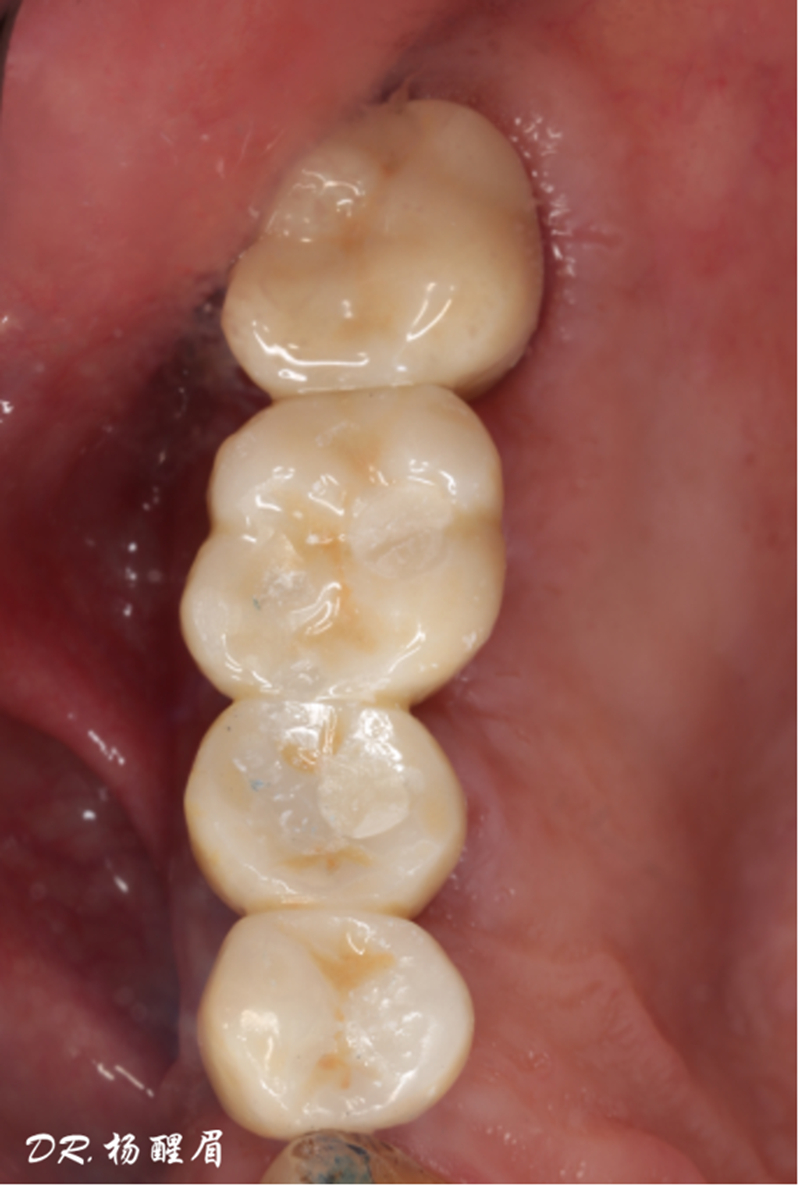

檢查:患者14、15、16、17缺失,無紅腫潰瘍,牙齦情況良好,口腔衛(wèi)生狀況良好。

診斷:14、15、16、17缺失

®袖口形態(tài)

®基樁形態(tài)

修復完成